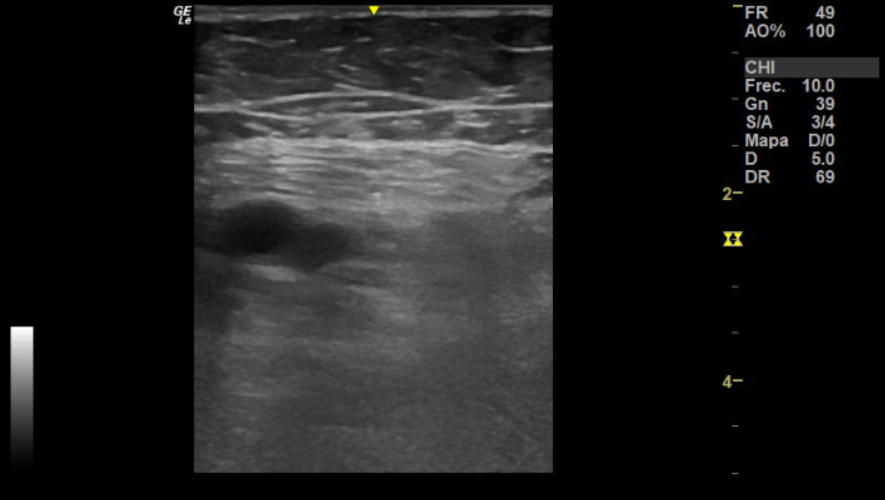

Se realiza ecografía de compresión a pie de cama, negativa en femoral derecha. Femoral izquierda no compresible por completo y con relleno incompleto de flujo Doppler, sin clara imagen de trombo en su interior.

El diagnóstico principal, basado en la sospecha clínica y prueba de imagen, fue de trombosis venosa profunda (TVP) femoral izquierda.

La ecografía fue clave para la identificación de la TVP femoral, lo que permitió la elección de un tratamiento dirigido. Este caso resalta la necesidad de considerar la TVP como diagnóstico diferencial en pacientes de edad avanzada con síncope, especialmente en presencia de factores de riesgo como inmovilidad o signos clínicos de trombosis. La colaboración entre atención primaria y urgencias es esencial para la detección y manejo adecuados de esta patología.